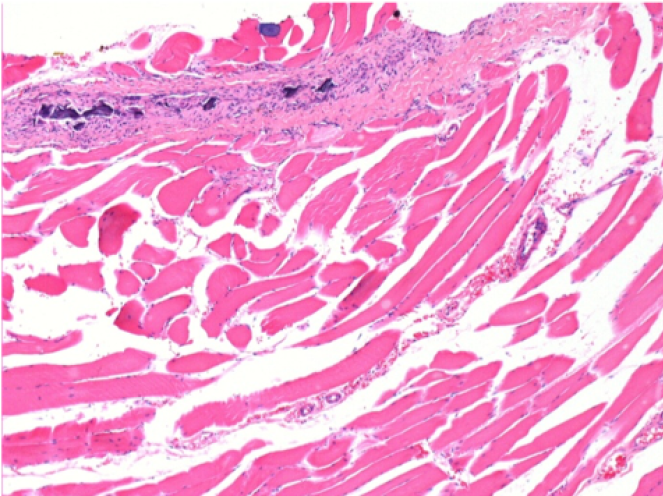

0.5 ml ( 5x 0.1ml) Endopeel SC Injection in the right subcutaneous pretibial area.

L:200x-Control-SC

R-D10-SC-200X

R-D30-SC-200X

R-D90-SC-200X

R-D210-SC-200X

R-D210-SC-400X